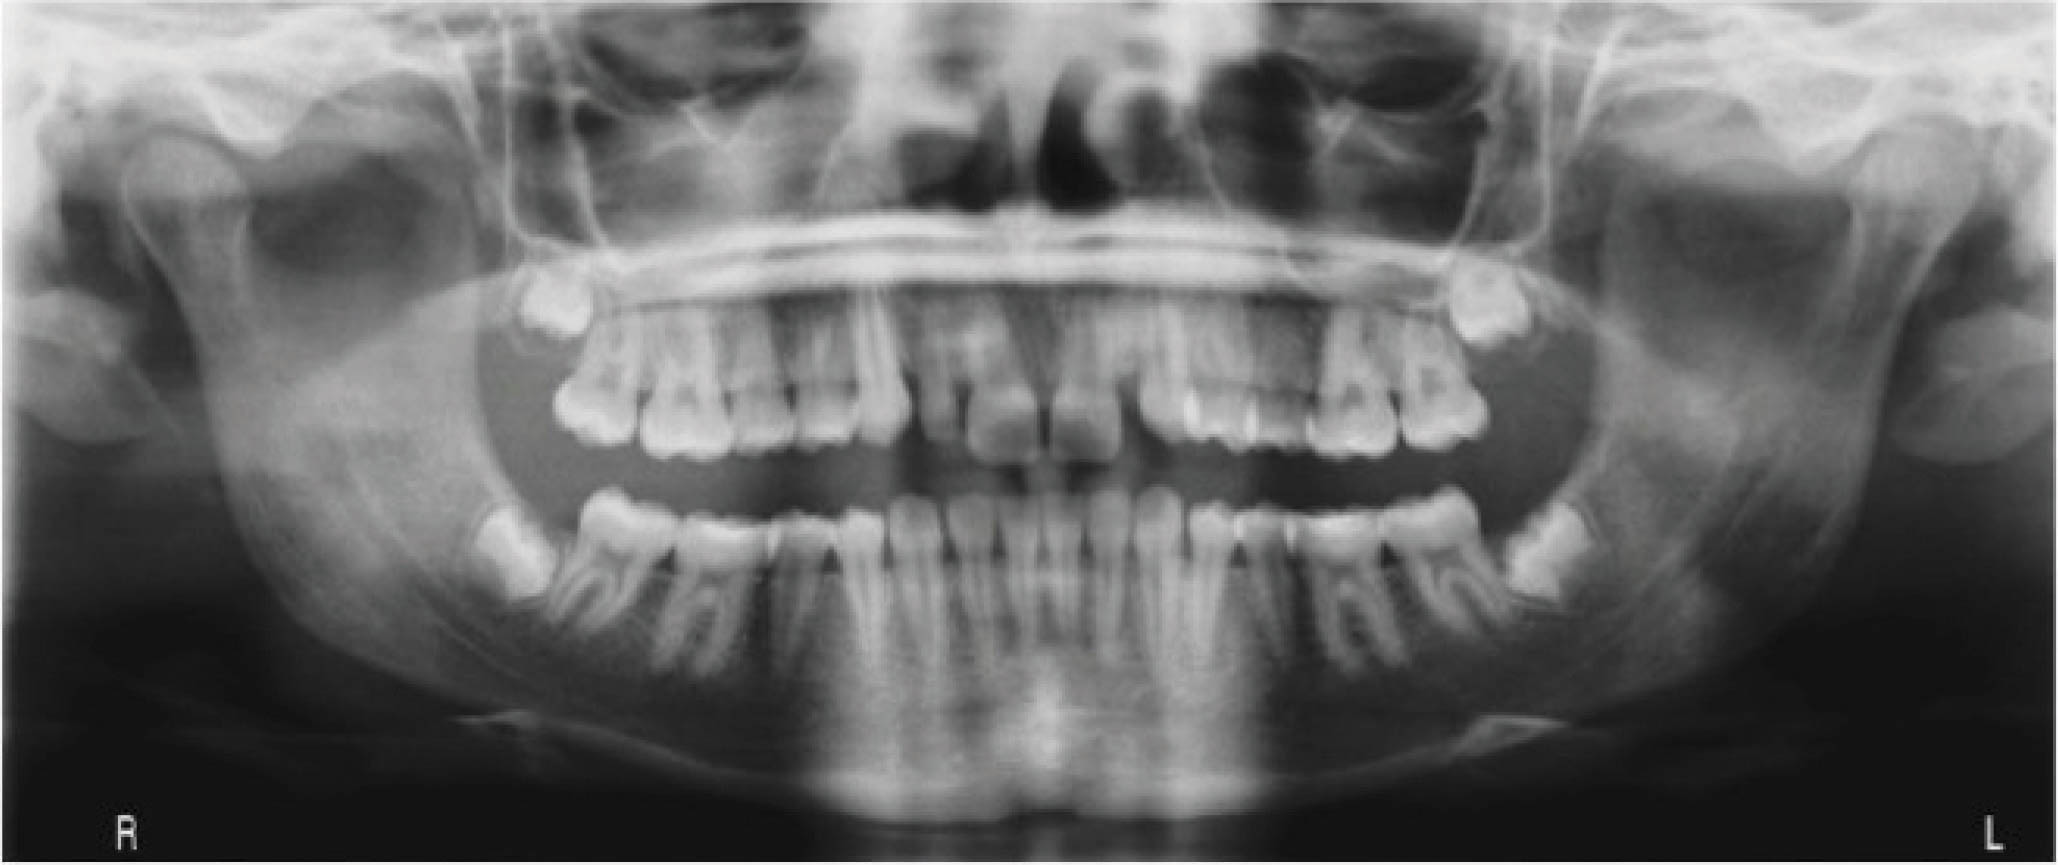

بیمار دیگر (شکلهای 50-6 الی 52-6): لترال چپ بالا را ندارد. هدف دیستاله نمودن کانین چپ بالا و هدایت آن تا رسیدن به رابطه کلاسI کانینی و نهایتاً قرار دادن یک ایمپلنت در ناحیه لترال است. اگر به OPG او نگاه بندازید، میبینید که لترال چپ بالا وجود ندارد و لترال راست بالا هم peg shape است.

: باید به لابراتوار بگوییم که تیپ دیستالی بیشتر به ریشه کانین چپ بالا بدهد. این زاویه بیشتر برای بیومکانیک کار است تا دندانها تیپ نشوند. باید در این بیمار هم همین کار را انجام داد. از آنجایی که قرار است کانین چپ بالا دیستالی بشود، احتمال دیستالی شدن تاج و مزیالی شدن ریشه وجود دارد. این حالت نه تنها مدنظر نیست، بلکه فضای کافی هم برای قرار دادن ایمپلنت به ما نمیدهد. بنابراین باید زاویه بیشتری به ریشه بدهیم تا در نهایت یک حرکت بادیلی داشته باشیم.

در OPG نهایی، کانین راست بالا در جایگاه صحیح است و فضا کافی برای ایمپلنت هم به وجود آمده است (کل درمان ۲۰ ماه به طول کشید). در این بیماران، باید حتماً درمان اضافه را در طراحی کامپیوتری در نظر بگیرید تا حرکتها بادیلی بشوند.

شکل 50-6

شکل 51-6

شکل 52-6